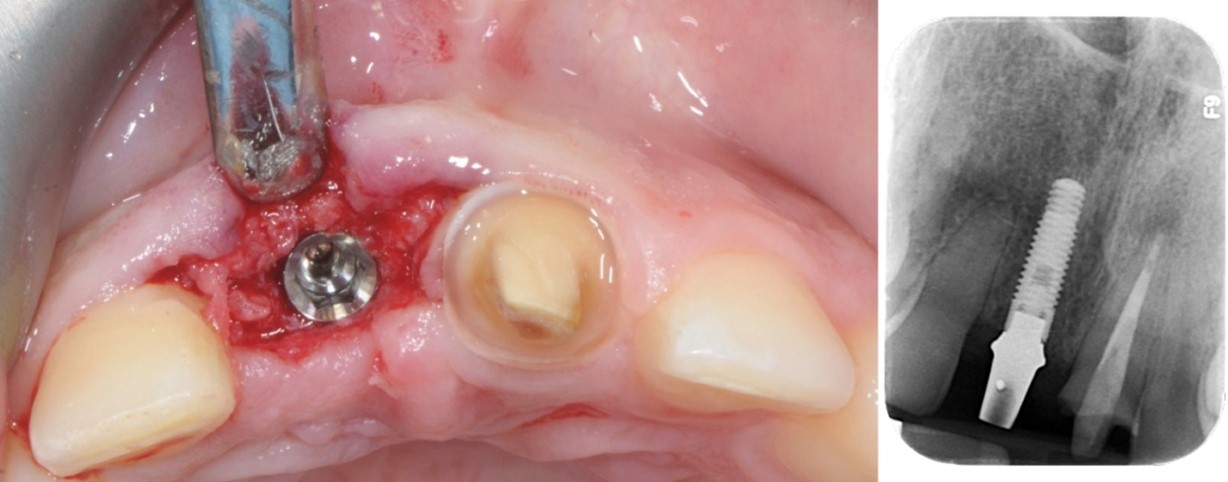

Immagine clinica e radiografica al momento della rimozione della membrana

Inserimento implantare dopo quattro mesi